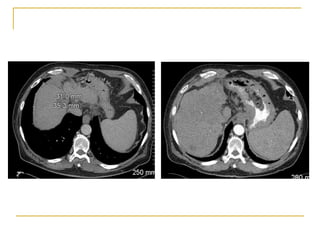

80 patients with HCC 3- 8cm (mFUP 32m)

CP A and B

< UNOS T4

23 with recurrent disease

Lesion size

52 - 3-5 cm

28 - 5-8 cm

Results

Complete ablation – 87.5%

94% cw 75% depending on size

22% local recurrence

15% vs 41% depending on size

Location near bile duct

54% distant recurrence

More frequent in recurrent HCC

Complications – 7.5% without mortality

1 tract seeding

Liu 2012 Clin Radiol 2012: 68;21

Role for microwave in larger lesions

Survival 1 2 3 5 years 81% 68% 56% 34%